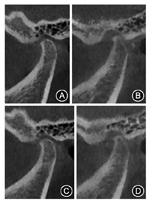

面像锥形束CT未见明显骨关节破坏,右侧髁突位于关节窝中央,左侧髁突较右侧髁突小,居关节窝后位。

咬合功能和美学效果的诊断和评价:患者初戴诊断饰面时偶有双侧耳前区轻度不适及夜间紧咬牙,2~3周后主观症状完全消除,咀嚼功能提高。锥形束CT示增加垂直距离后关节前后间隙较治疗前无明显改变(图4)。戴用9个月后牙齿咬合关系无明显变化,表明颌位关系稳定,双侧上颌尖牙有部分崩脱和磨耗,提示侧方咬合时引导牙尖的引导斜面斜度偏大,需要调整。而上前牙牙齿形态和排列还需进一步调整。根据功能和美学的调整要求,制作临时冠,确定上前牙最终形态(图5)。